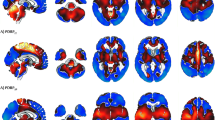

Selection of HC images was based on visual rating, after Cook’s distance and jack-knife analyses, to exclude artefacts and/or outliers. The performance of these HC datasets (ADNI-HC and AIMN-HC) to extract hypometabolism patterns in single patients was tested in comparison with the standard reference HC dataset (HSR-HC) by means of Dice score analysis. We evaluated the performance and comparability of the different HC datasets in the assessment of single-subject SPM-based hypometabolism in three independent cohorts of patients, namely, ADD, bvFTD and DLB.

Two-step Cook’s distance analysis and the subsequent jack-knife analysis resulted in the selection of n = 125 subjects from the AIMN-HC dataset and n = 75 subjects from the ADNI-HC dataset. The average concordance between SPM hypometabolism t-maps in the three patient cohorts, as obtained with the new datasets and compared to the HSR-HC standard reference dataset, was 0.87 for the AIMN-HC dataset and 0.83 for the ADNI-HC dataset. Pattern expression analysis revealed high overall accuracy (> 80%) of the SPM t-map classification according to different statistical thresholds and sample sizes.